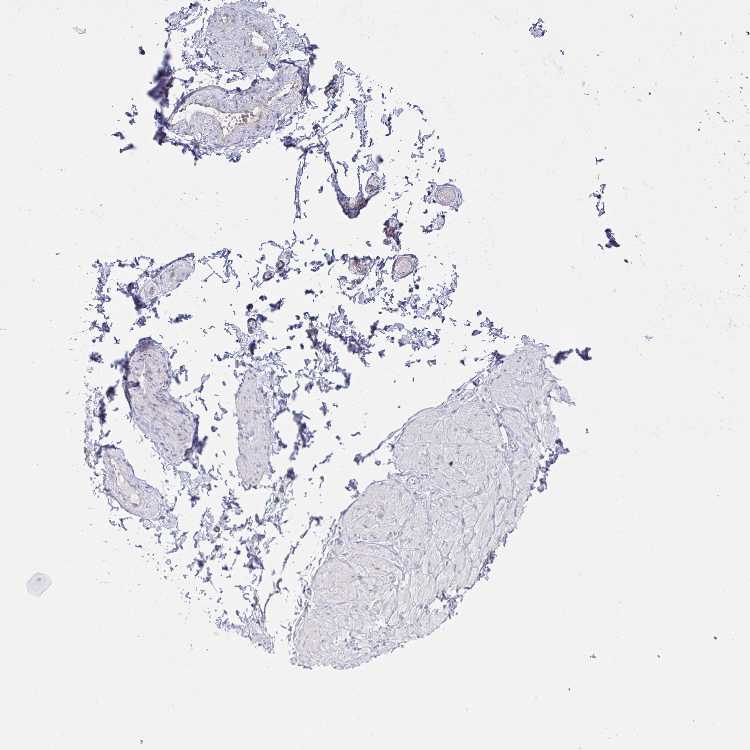

ADIPOSE TISSUE - Antibody stainingi

Antibody staining in the annotated cell types in the current human tissue is reported as not detected, low, medium, or high, based on conventional immunohistochemistry profiling in selected tissues. This score is based on the combination of the staining intensity and fraction of stained cells.

Each image is clickable and will lead to virtual microscopy that enables deeper exploration of all samples and also displays staining intensity scores, fraction scores and subcellular localization as well as patient and tissue information for each sample.

Antibody HPA037675Antibody HPA037676Antibody CAB010345

Adipocytes Not detectedNot detectedMedium